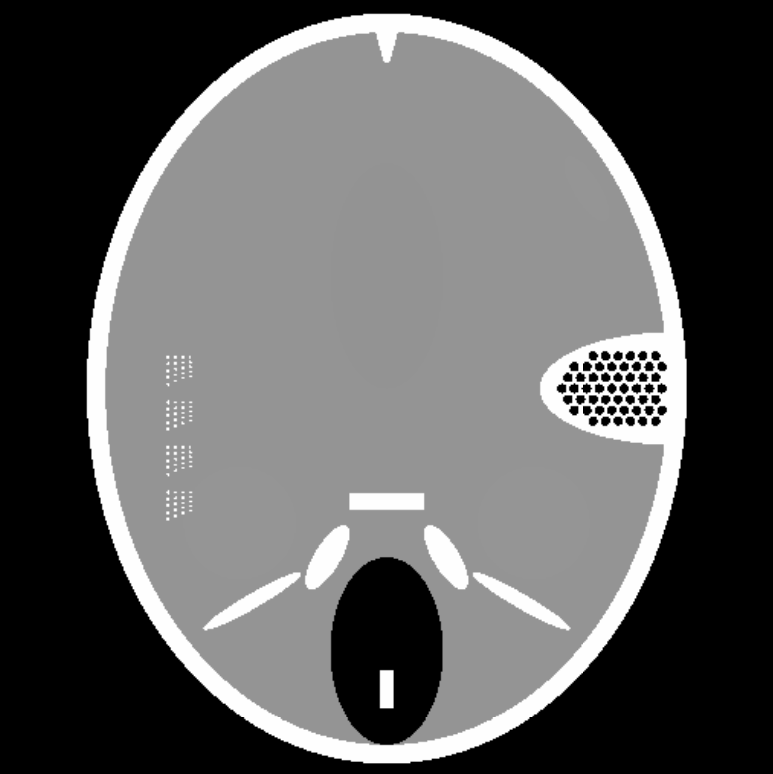

We compare the computation time and SNR of back projection among oblique method, orthogonal method under band limited assumption and box spline methods. We throughly test the performance of oblique method, box spline methods and blurred box spline method (box spline method with detector blur effect). Three images are used in our experiments, the first one consists of randomly placed ellipses, the second one is Forbild head phantom, and the last one is a real CT image from LIDC-IDRI dataset [13] (Fig.2). In our experiments, we fix the sampling steps to be equal in all dimensions, 𝚲x=λxI2subscript𝚲𝑥subscript𝜆𝑥subscript𝐼2\boldsymbol{\Lambda}_{x}={\lambda}_{x}I_{2} and λy=nλxsubscript𝜆𝑦𝑛subscript𝜆𝑥\lambda_{y}=n\lambda_{x}, where n𝑛n is the downsampling rate. The number of views is set to 180180180. Signal to noise ratio (SNR) in dB and structural similarity index (SSIM) are measured for all the methods. All computations were done on one PC (Windows 10 with a 3.7GHz 6-Core Intel Core i7-8700K processors and 32GB of RAM) using Matlab.

Refer to caption

(a)

(b)

(c)

Fig. 2: The three images used in our experiments. (a) Spots. (b) Forbild phantom. (c) A real CT image.